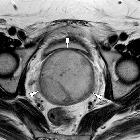

Radiographic features

MRI

In the pelvis may add further to CT in delineated the tumor's relationship to adjacent organs and identifying lymph node disease.